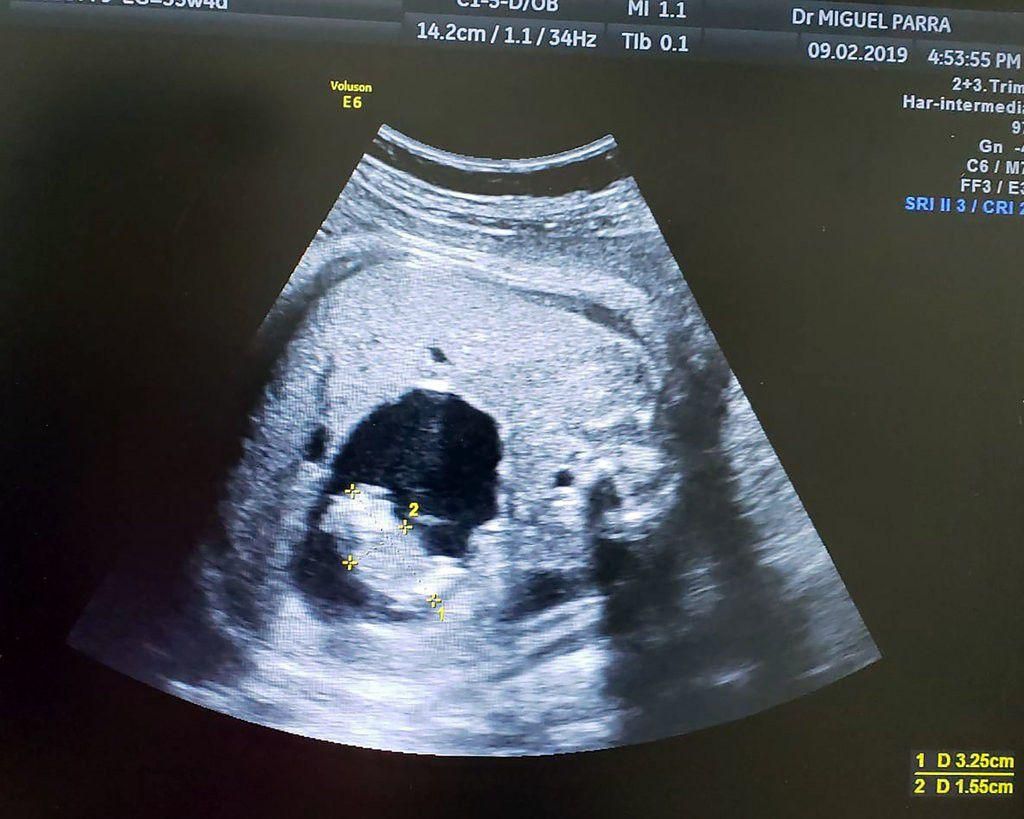

Originally, docs thought that the fetus had a cyst on her liver. But that all changed when the mother, Monica Vega, visited Miguel Parra-Saavedra, MD, a high-risk pregnancy specialist in Baranquilla, Columbia. Parra-Saavedra was able to see that the believed-cyst was actually a tiny infant who was "supported by a separate umbilical cord drawing blood where it connected to the larger twins intestine," per The New York Times -which is why the smaller fetus is frequently known as a parasitic twin.

The twin fetus.

Anyway, two weeks later, at 37 weeks gestation, Vega gave birth via c-section to a seven-pound baby girl named Itzamara. And just one day later (!!), the newborn underwent laparoscopic surgery to remove the fetal twin, who measured at about two inches long, Parra-Saavedra told The New York Times .